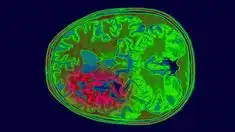

4. 진단은 MRI, CT 스캔을 통해 이루어지며, 조직 검사로 확진합니다.

교모세포종의 진단은 주로 고해상도의 영상 진단 도구인 MRI 또는 CT를 통해 이루어집니다.

이러한 검사를 통해 종양의 위치, 크기 및 주변 조직과의 관계를 정확히 평가할 수 있습니다.

또한, 최종적인 진단을 위해서는 조직 검사가 필수적으로 수행됩니다.